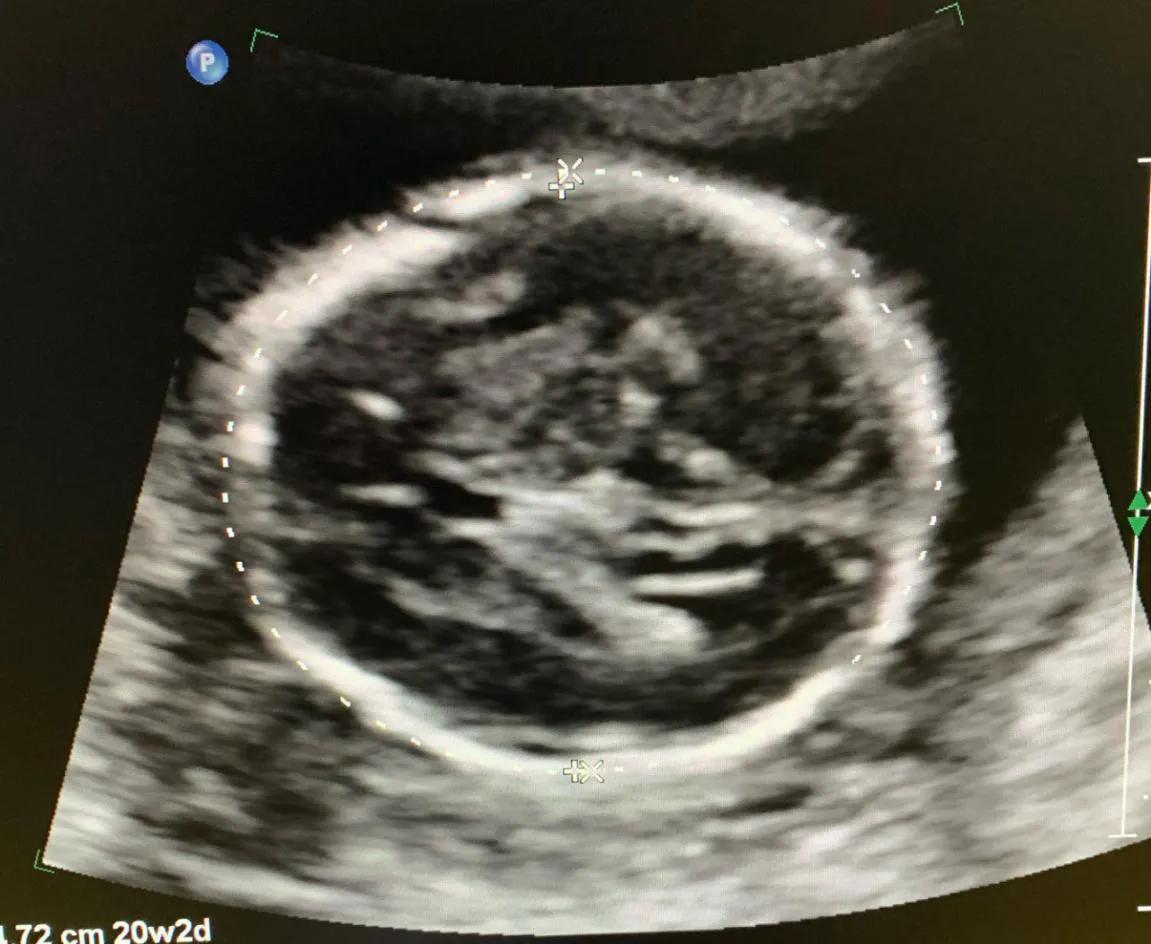

第三次超声检查

孕20-24周,检查项目:产前诊断三级筛查,俗称大畸形筛查,也叫大排畸。主要为检查胎儿是否患有重大结构畸形,可以排除胎儿大的结构畸形,如无脑儿、脑膨出、胸腹壁缺损内脏外翻、单心腔、致死性软骨发育不良、严重的脊柱裂等。耗时较长,当胎儿体位不佳时,需要适当走动再次检查。

注意事项:三维、四维不是产前III级筛查必须检查。我们的大排畸超声,不是用三维四维来进行诊断和观察的,就像照相馆,你可以看到你认识的照片,但是摄影师不会也不可能告诉你,照片中的人是否得病了一样,三维是给您能看得懂的表面照片,不能穿透性的看到胎儿内部结构。所以,您在做排畸的时候,屏幕上显示的图(比如图3,就是排畸时候的胎儿头颅的图像),可能您都看不懂。

图3 胎儿结构畸形筛查时头颅双顶径切面图